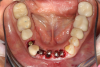

Fig 5. Occlusal view of completed zirconia with porcelain application on teeth Nos. 29, 30, and 31.

Figure 5